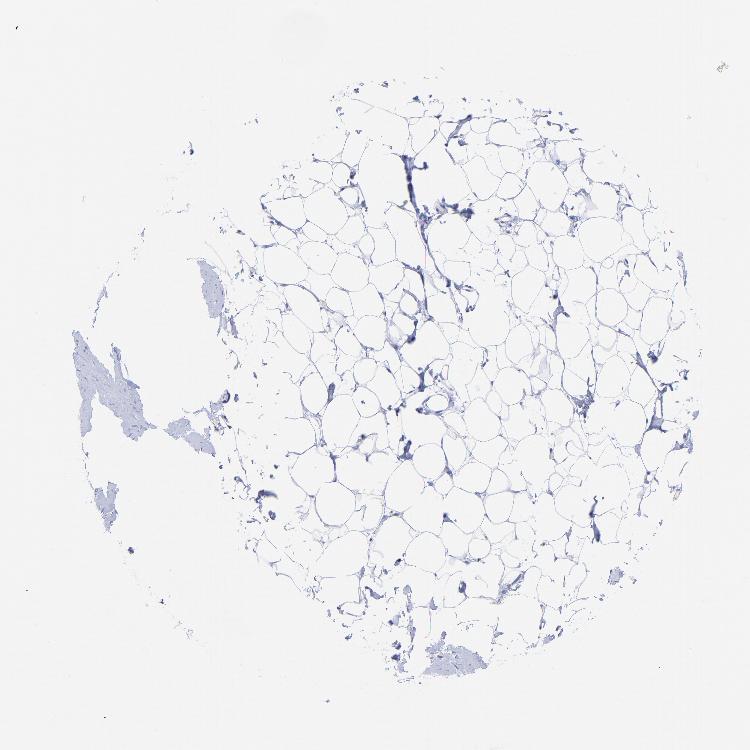

Adipocytes Not detectedNot detectedNot detected

Glandular cells LowNot detectedHigh